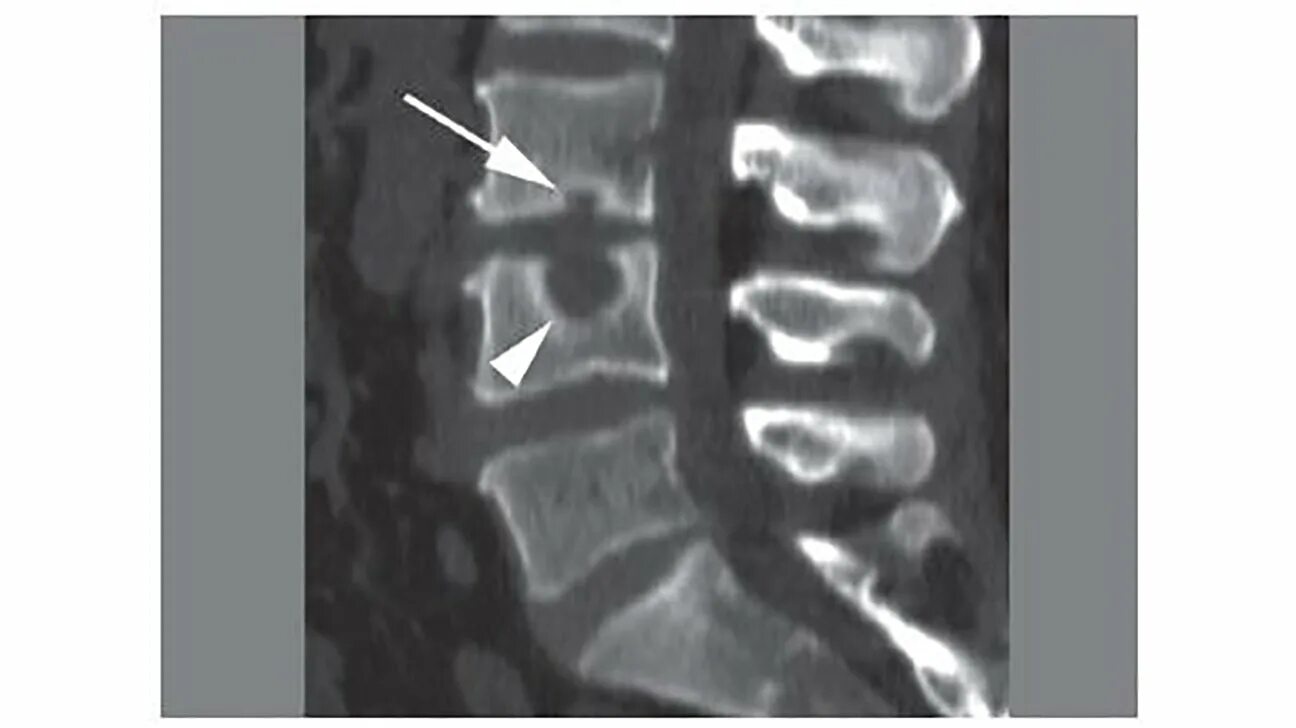

Узлы шморля в грудном отделе что это